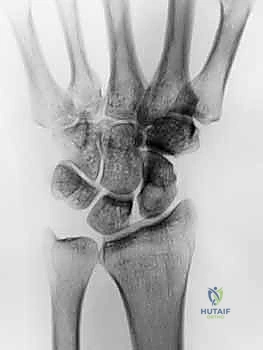

لفهم مدى تعقيد جراحة بتر مفصل الورك، يجب أولاً إدراك العظمة الهندسية والتشريحية لهذه المنطقة الحيوية من جسم الإنسان. مفصل الورك ليس مجرد نقطة اتصال؛ بل هو محور الارتكاز الأساسي الذي يحمل وزن الجزء العلوي من الجسم ويوجهه نحو الأطراف السفلية، مما يتيح لنا المشي، الجري، والوقوف.

- عظام الحوض (Pelvis): تتكون من اندماج ثلاثة عظام رئيسية (الحرقفة، الإسك، والعانة). تحتوي هذه العظام على تجويف عميق يُعرف بـ "الحُق" (Acetabulum)، وهو المكان الذي يستقر فيه رأس عظم الفخذ ليشكل مفصلاً من نوع "الكرة والتجويف" (Ball-and-Socket Joint).